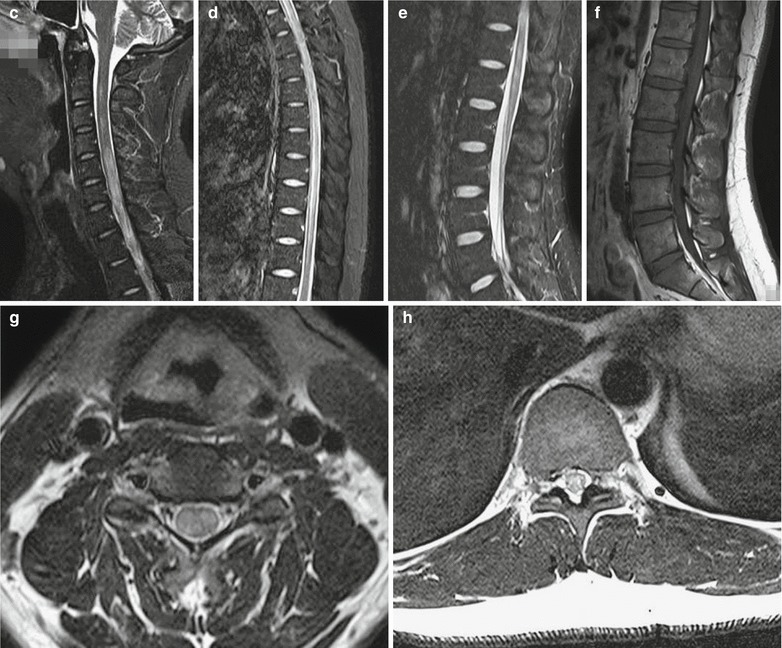

Measles Pneumonia in Children

Typical measles pneumonia in children is mainly characterized by interstitial inflammation, with grid-like lung markings. The lesions are mainly distributed in both middle and lower lungs with accompanying small spots and flakes of blurry shadows (Fig. 23.3). The common changes also include widened right upper mediastinum, increased transparency of lung fields, and emphysematous changes. The incidence rate of enlarged and thickened hilar shadow is higher in children than in adults.

Fig. 23.3.

Pediatric measles pneumonia. At day 4 after hospitalization, X-ray demonstrates thickened and blurry pulmonary markings in both lungs, small grid-like shadow at the middle and medial parts of left upper lung, and flakes of blurry shadows at the right lower lung hilum

Case Study 2

A girl aged 5 years complained of fever for 6 days as well as rashes, coughing with sputum for 4 days. Red maculopapules were observed at the face, chest, abdomen, back, and limbs.